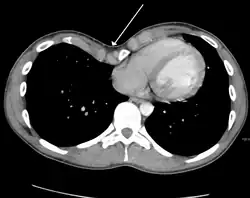

Masses

Masses such as tumors can also cause compression and displacement of mediastinal structures. There are various mediastinal tumors, and they are classified by their location in the chest. Notable examples include germ cell tumors and lymphomas.[12] Teratomas are a class of germ cell tumors that arise in the chest due to failure of germ cell migration during development. They can expand to large sizes and cause hemoptysis and pleural effusion. Radiographic features of teratomas typically include fluid and fat but also muscle, teeth, and bones inside the mass.[13]